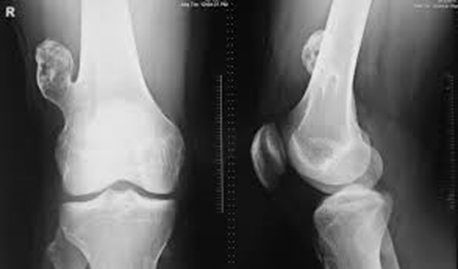

Multiple osteochondroma

The images show a case of multiple osteochondroma which was operated by

Dr. Zenios in order to restore the mechanical axis.

Pre-operative